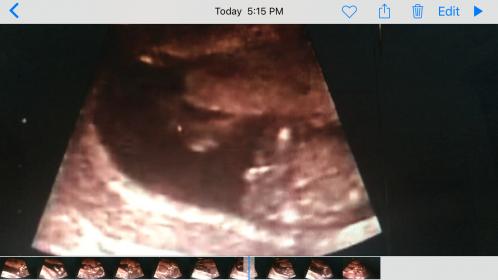

Hello, this is my baby, 15w3d, can anyone tell boy or girl, thank you. Attachment 27834